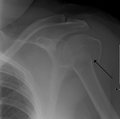

Proximal humerus fracture